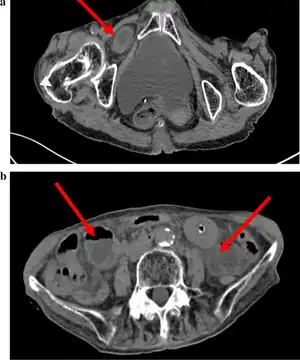

Abdominal CT scan showing obturator hernia[1]

The diagnosis is often made during laparoscopic pelvic exploration after the person arrives at the hospital with signs and symptoms consistent with bowel obstruction. Laparoscopic pelvic exploration is a minimally invasive procedure that allows the surgeon to visually examine the contents of the abdomen without making a large cut.[5] The Howship–Romberg sign is suggestive of an obturator hernia, with about 56.2% (out of 146 patients in a systematic review) of people showing these signs.[2] These signs are worsened by thigh extension, medial rotation and abduction.[6] It is described as a sharp, stabbing pain in the medial thigh/obturator distribution, extending to the knee and is caused by the hernia pushing on the obturator nerve. The Hannington-Kiff sign can also be suggestive of an obturator hernia, which tests the adductor muscle reflex with a hammer whilst applying pressure on the obturator nerve.[7] However, due to its rare form, obturator hernias are difficult to diagnose due to many other possibilities, non-specific symptoms of pain, as well as minimal external signs/symptoms that can be seen without imaging. The current gold-standard for diagnosis of an obturator hernia is through abdominal computed tomography scans (CT scans), which has been used for diagnosis of 84.2% of patients in a recent systematic review for obturator hernias.[2]